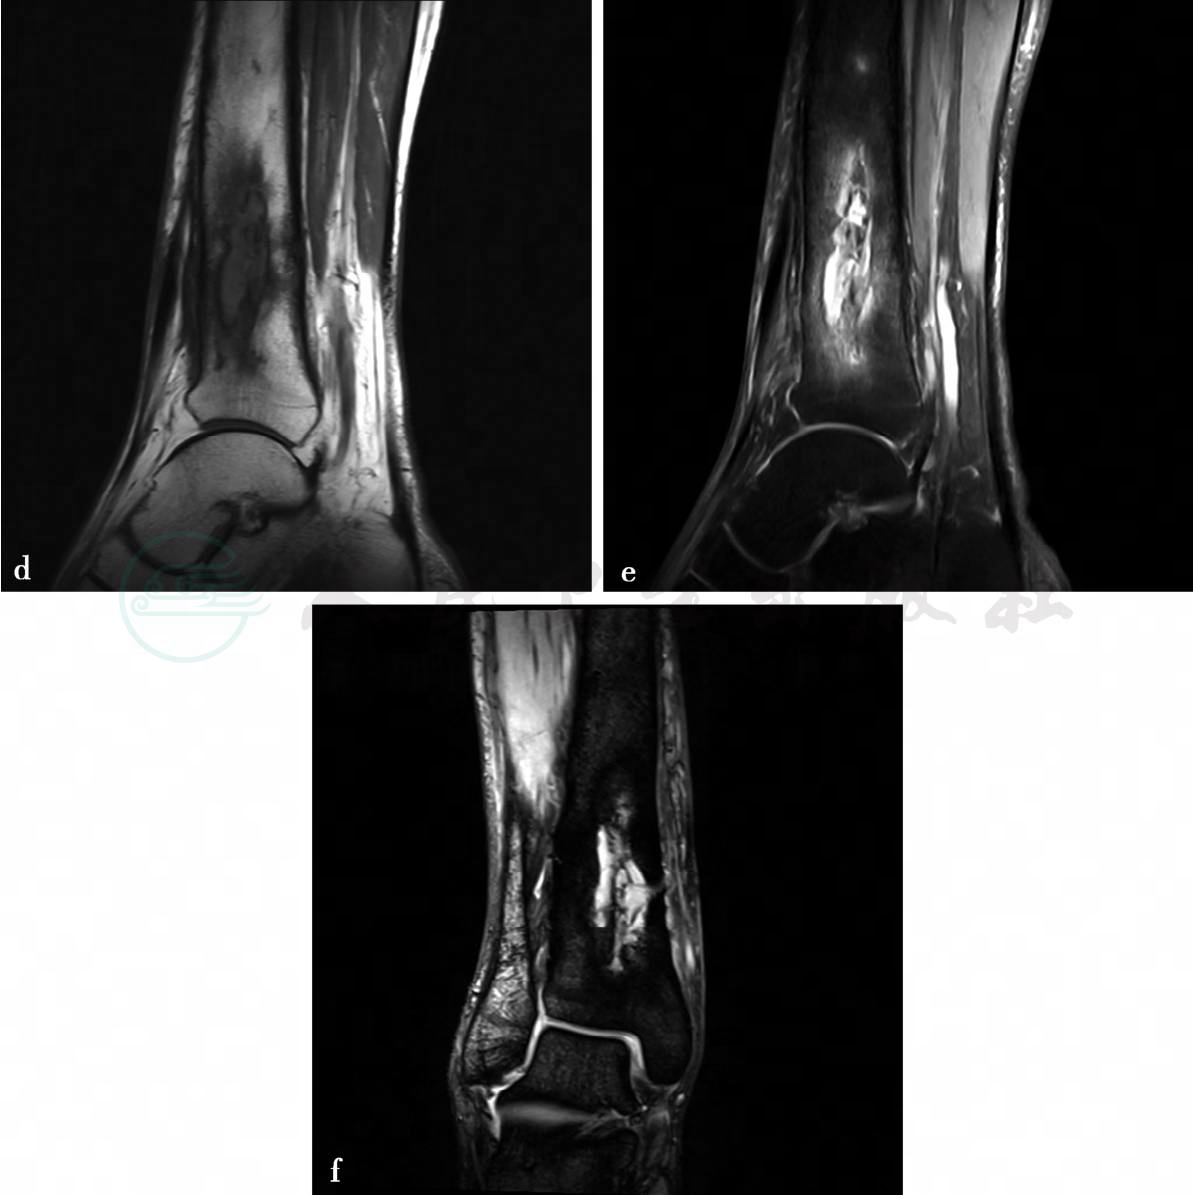

(2)病例5:

MRI平扫及增强扫描。

图2 图2d~f,MRI平扫示右胫骨中下段骨干增粗,骨皮质不均匀增厚,骨髓腔内可见溶骨性骨质破坏。图2d,T1WI上呈低信号。图2e,T2WI脂肪抑制像上呈稍高信号。图2f,MEDIC序列像上呈高信号,信号不均匀,可见斑点状低信号和窦道形成;周围软组织明显肿胀